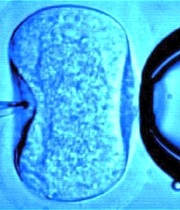

EImagendwards, "padre" del primer bebé probeta, la británica Louise Brown (1978), comenzó sus investigaciones sobre la fecundación in vitro a mediados de la década de 1950, planteando la posibilidad de extraer un óvulo, fecundarlo con esperma en un laboratorio y volver a introducirlo posteriormente en el cuerpo de la mujer.

Así, el ganador de la presente edición del Nobel de Medicina logró que el 25 de julio de 1978 naciese el primer niño fruto de una fecundación in vitro.

A los trabajos de Edwards y Steptoe se debió el nacimiento, en julio de 1978, de la niña Louise Brown, el primer bebé probeta del mundo y un acontecimiento histórico, en palabras del Instituto Karolinska.